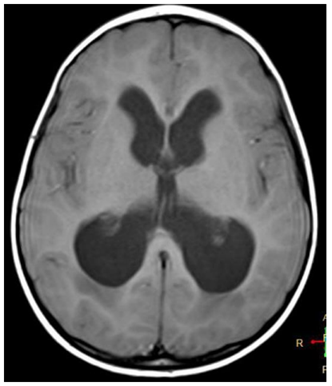

RM de paciente encontrado irresponsivo, com tempo de início dos sintomas desconhecido.

Baseado nesse exame, assinale a afirmativa correta.